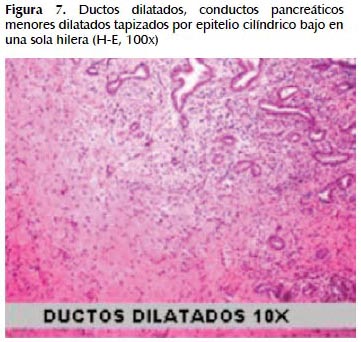

La alteración fundamental en este caso es la presencia de marcada dilatación de los conductos pancreáticos (Figuras 6, 7, 8, 9, 10 y 11) con variable hiperplasia de los conductos menores periféricos.

Los quistes están limitados por células ductales altas, algunas mucinosas, en su mayor extensión dispuestas en una fila. De manera focal se ve proyecciones papilares del epitelio y también focos de erosión con reacción inflamatoria, exudado linfocitario y formación de tejido de granulación.

El resto del parénquima pancreático muestra múltiples focos de autolisis y variable hiperplasia de los ductos.